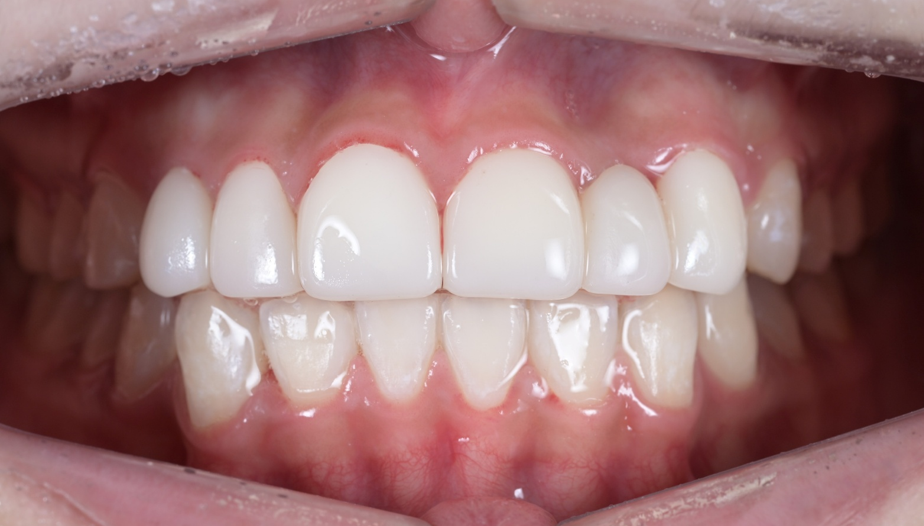

4단계: 최종 보철물 세팅 – 완성된 미소

임시치아 단계에서 확인된 형태를 바탕으로 최종 보철물을 제작했습니다. 최종적으로 좌우 대칭성, 치아 간 비율, 잇몸 라인의 조화가 모두 달성되었습니다. 그리고 무엇보다 기쁜 점은, 모든 치아의 신경을 살린 채 (생활치 상태로) 치료를 완료했다는 것입니다. 꼭 필요한 부분만 최소한으로 삭제하여 신경치료 없이 마무리할 수 있었습니다.

최종 보철물이 세팅된 모습 – 자연스럽고 조화로운 미소가 완성되었습니다

Before & After – 치료 전후 비교

치료 전과 후를 비교해보면, 그 변화가 확연히 드러납니다.

| 치료 전 (Before) | 치료 후 (After) | |

|---|---|---|

| 치아 형태 | 왜소치, 잔존유치, 결손 존재 | 자연스럽고 균일한 치아 형태 |

| 잇몸 라인 | 좌우 비대칭, 불규칙 | 좌우 대칭, 조화로운 라인 |

| 치아 비율 | 앞니가 상대적으로 크고 부조화 | 전체적으로 조화로운 비율 |

| 전체적 인상 | 불규칙하고 비심미적 | 자연스럽고 아름다운 미소 |

교정 + 잇몸성형 + 심미보철이라는 종합적 접근이 만들어낸 결과입니다. 환자분도 치료 결과에 매우 만족해하셨습니다.